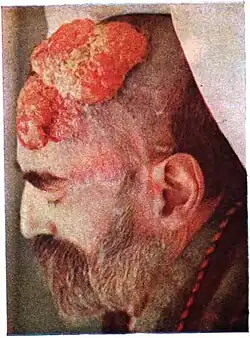

| Dermal cylindroma treated with X-rays without recurrence |

In dermatologic pathology, a dermal cylindroma, also dermal eccrine cylindroma or cutaneous cylindroma[1]: 666 ) and (less specifically) cylindroma, is a benign adnexal tumor[2] that occurs on the scalp and forehead.

Multiple cylindromas may grow together in a "hat-like" configuration, sometimes referred to as a turban tumor.[3] Cylindromas are uncommon dysplasias of skin appendages.[4]